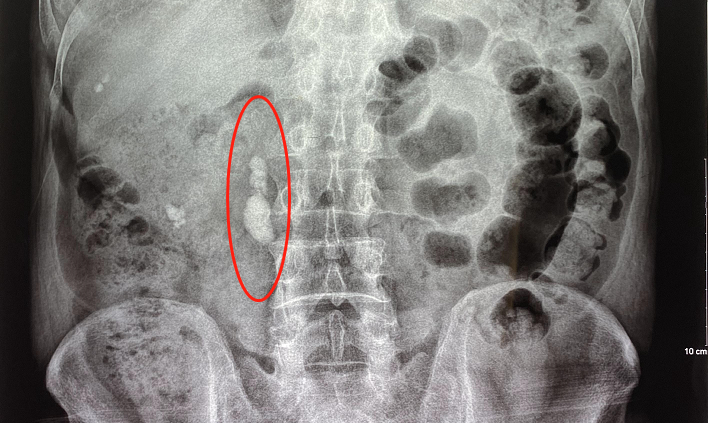

输尿管结石

输尿管结石大部分都是从肾脏里掉出来的,当结石堵塞在输尿管时,则被称为输尿管结石。

当其嵌顿在输尿管上段时,会出现剧烈“肾绞痛”,同时会伴随发热、恶心、呕吐、冷汗等症状,严重时甚至会出现休克,发病时会伴随血尿。

结石堵塞在输尿管下段时,可引起尿频、尿急、尿痛等膀胱刺激症。